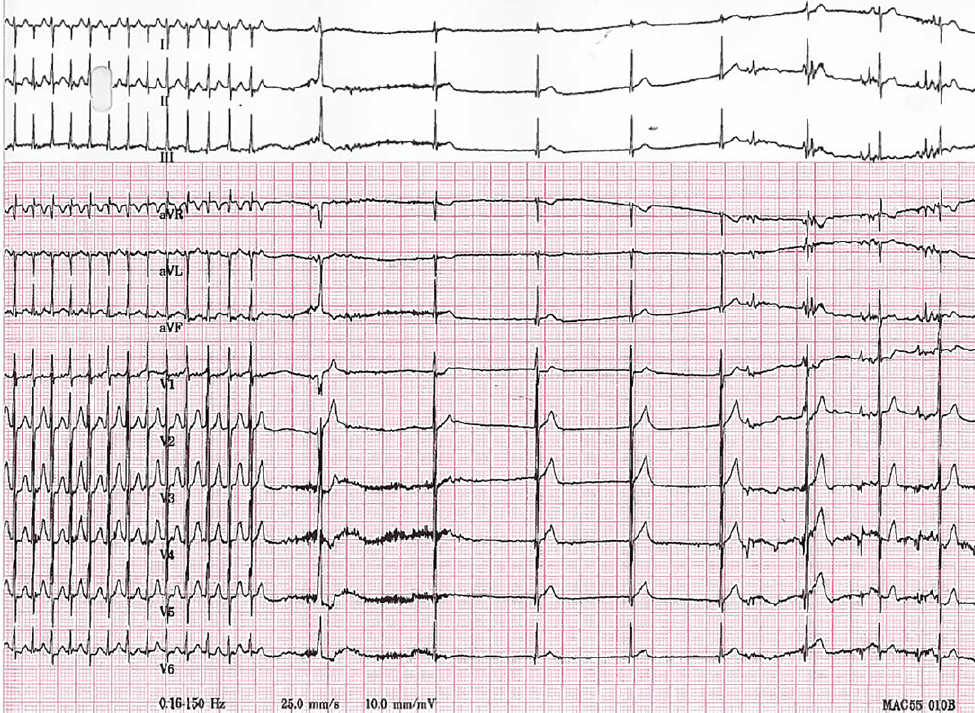

・HR299bpmとなりER受診となった

・ECGではnarrow QRS tachycardiaを認めた

・患者はHR166bpmまで落ち着き、洞調律に復帰した